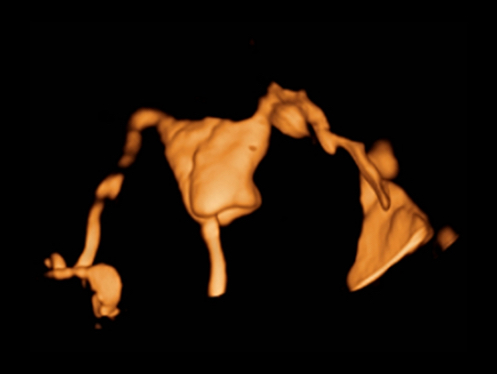

El ecГіgrafo DC-80A con X-Insight proporciona una soluciГіn excepcionalmente inteligente para la completa salud de la mujer, desde fertilidad hasta el cribado prenatal y asistencia sanitaria posparto.